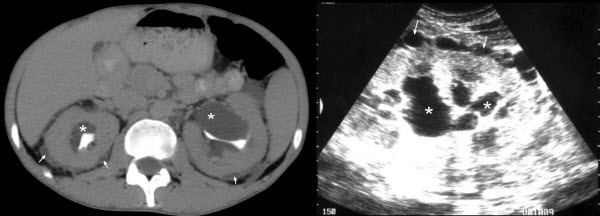

referred abdominal pain

Abdominal pain - 4386.4.jpg

Abdominal pain - 4893.png

Acute abdominal pain.